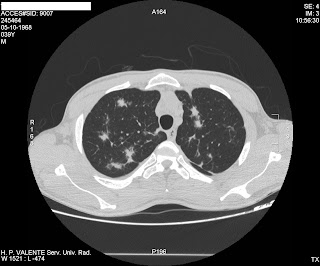

Young male with clinical information of HIV and Pulmonary Tuberculosis

This CT change the diagnosis. What you think?

There are multiple bilateral areas of flame shaped consolidation.No zone predilection. Of course TBC is often in HIV pts and should always be in the differential. In HIV pts, pulmonary tuberculosis can appear wherever and there is no radiological pattern that can exclude it. The key question is if this patient has a bacteriological diagnosis (sputum/washings/gastric fluid). The abscence of cavitation is against TBC BUT this CANNOT rule it out. Personally, this radiological pattern (FLAME shaped nodular areas of consolidation)is highly suggestive of sarcoma KAPOSI. The differential also includes - pulmonary lympoma - fungal infection (although no halo sign is seen) - viral infection - common pathogens In clinical practice I think it should be treated as common pneumonia until proven otherwise, keeping in mind that TBC, fungal, viral infections are a possibility. Since sarcoma Kaposi is highly suggestive by CT a bronchoscopy (with BAL/transbronchial biopsy) or even VATS/lung biopsy should follow if the patient won't respond to the antibiotic therapy or if other pathogens are identified. Thank you. P.S. You're doing a nice job. Keep it up. This blog can be very educational!

Thank´s for your kind words Vasilios. Very important for us. Great comment and diferencial. After the CT the patient underwent a bronchoscopy that confirm Kaposi.

There are multiple bilateral areas of flame shaped consolidation.No zone predilection.

Of course TBC is often in HIV pts and should always be in the differential. In HIV pts, pulmonary tuberculosis can appear wherever and there is no radiological pattern that can exclude it. The key question is if this patient has a bacteriological diagnosis (sputum/washings/gastric fluid). The abscence of cavitation is against TBC BUT this CANNOT rule it out.

Personally, this radiological pattern (FLAME shaped nodular areas of consolidation)is highly suggestive of sarcoma KAPOSI.

In clinical practice I think it should be treated as common pneumonia until proven otherwise, keeping in mind that TBC, fungal, viral infections are a possibility. Since sarcoma Kaposi is highly suggestive by CT a bronchoscopy (with BAL/transbronchial biopsy) or even VATS/lung biopsy should follow if the patient won't respond to the antibiotic therapy or if other pathogens are identified.